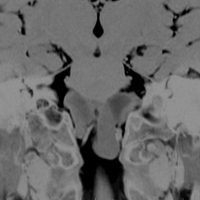

CTでは壁が厚く高密度,MRI T2強調画像では低信号,T1強調画像では高信号です。内部に血液を含んでいるようなのう胞に見えます。のう胞の壁は非常に厚く硬いものが予想されます。閉塞性水頭症になっています。

若い男性ですが,内視鏡手術では摘出できない壁がガチガチのものでした。モンロー孔が広いので経脳梁到達法 transcallsal approachで手術しました。右前頭部から入ろうとしましたが,架橋静脈のために入れず,左前頭葉を除けて,透明中隔の正中に達しました。ところが,左の脳弓が菲薄化して広がり腫瘍の上面にみえましたから,左のモンロー孔からは摘出できませんでした。しかたがないので,右のモンロー孔から腫瘍を摘出しています。腫瘍の周囲には第3脳室脈絡叢が広範囲に癒着していました。のう胞内容は暗褐色の古い血腫でした。のう胞の壁は硬く厚い結合織で肉芽腫のような肉眼所見でした。左右の脳弓にも癒着し,内大脳静脈にも癒着していたので,その部分には皮膜を残しました。

術後のMRIです。幸い,記憶障害などの脳弓症状はでませんでしたが,かなりリスクの高い手術でした。